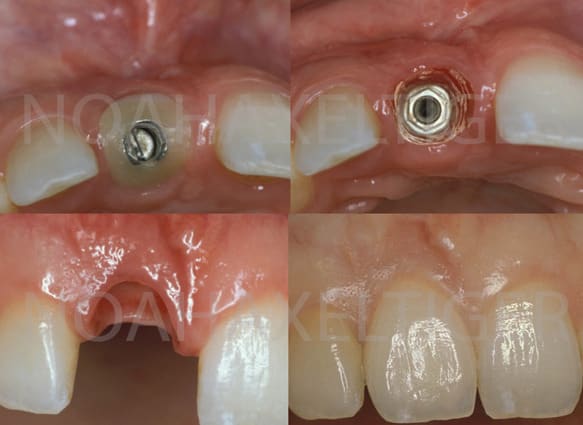

On peut également modifier un pilier de cicatrisation classique en pilier de cicatrisation personnalisé avec l'aide d'un peu de composite. C'est le meilleur compromis économique entre le pilier de cicatrisation du commerce et la couronne provisoire implantoportée qui permet d'obtenir des résultats esthétiques très satisfaisant.